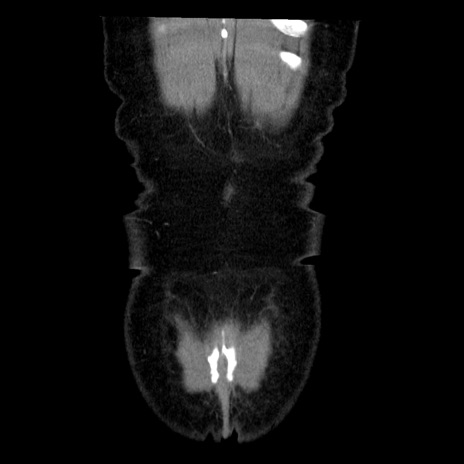

症例6(冠状断像)

【症例】50歳代女性

【主訴】下腹部痛

【現病歴】本日朝より下痢2回あり。 昼食を食べた後、嘔吐3回、下腹部痛認め、症状軽快せず、当院救急搬送。

最終食事:本日昼(生ものなし)。 昨日の夜、刺身を食ぺたとのこと。周囲に同様の症状の者なし。普段、排便は毎日あるとのこと。

【既往歴】卵巣癌術後(8年前に当院で卵巣摘出)

【身体所見】 意識清明、腹部:平坦、腸蠕動音→、やや硬、下腹部自発痛・圧痛あり、反跳痛あり、筋性防御なし。

【データ】WBC 16000、CRP 0.01